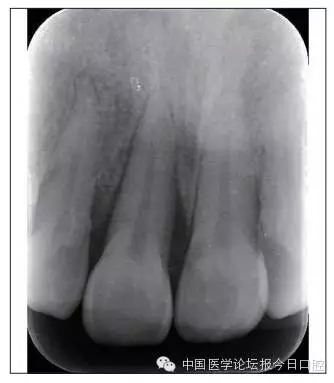

全口曲面體層片(圖3)顯示,患者全牙列牙槽骨吸收;根尖片(圖4)示11近中牙槽骨角形吸收已達根尖1/3,21牙槽骨嵴頂吸收至根1/2,23牙槽骨近中骨板角形吸收至根1/2。磨牙區(qū)骨嵴頂吸收3mm。治療前頭顱側位片見圖3,治療前ODS模型見圖5。

7.webp.jpg

圖4 治療前根尖片

矯治后,牙列間隙關閉,面型及覆(牙合)覆蓋改善。11根尖片(圖8)顯示,治療后較治療前,牙周支持組織增加,牙槽骨角形吸收區(qū)水平向縮小0.3mm,垂直向縮小0.6mm。11松動Ⅰ度,余切牙無松動。

本病例右上中切牙牙槽骨角形吸收,在盡量保證治療前后根尖片投照角度一致的情況下,以鄰牙作為校準,在根尖片上對治療前后的骨量進行評價,治療后牙槽骨角形吸收區(qū)水平向縮小0.3 mm,垂直向縮小0.6mm。盡管根尖片并不能說明骨量改變,但從影像學上能看到骨吸收區(qū)域有所減小。